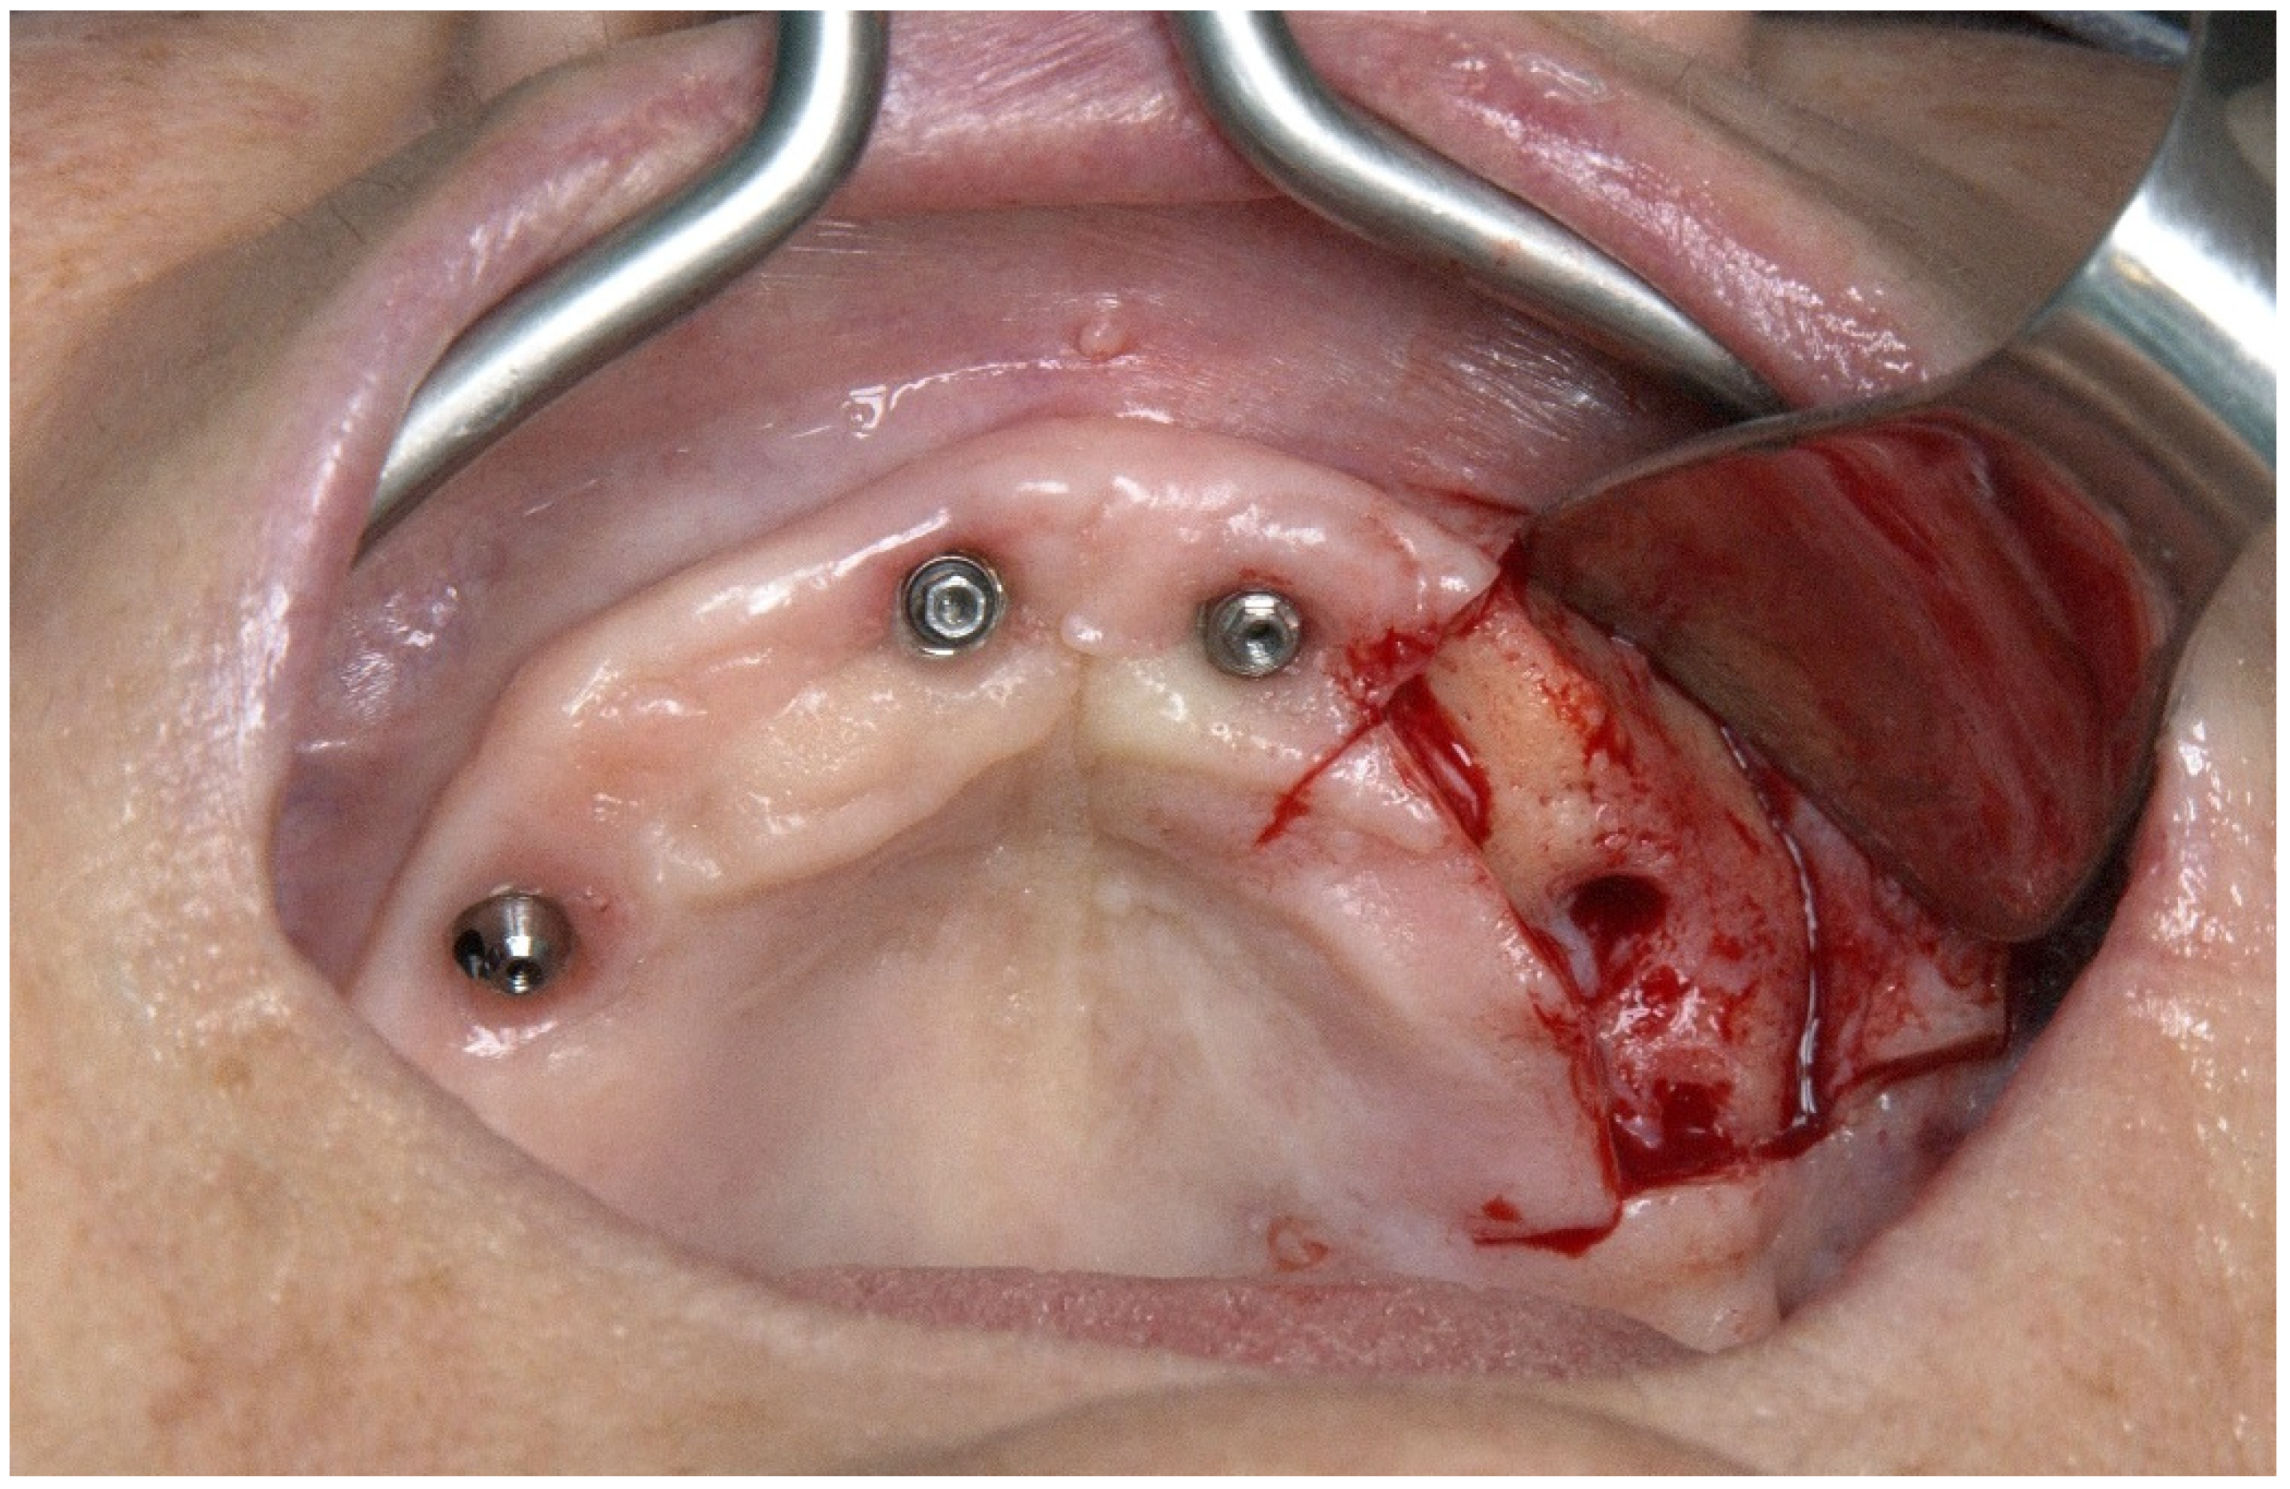

2.1. Patient 1